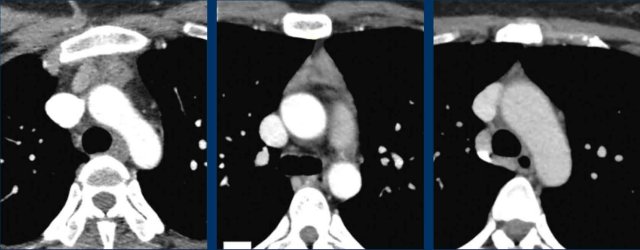

Lymphoma

These images are of a 60-year old female.

She had cardiac arythmias and on a chest CT an incidental mass was seen.

First study the images.

Question: what is the most likely diagnosis?

Images

The mass has a high density on the post contrast scan.

There is no macroscopic fat.

The border is somewhat irregular.

And there is a second mass (arrow). On other levels more masses were seen.

Discussion

When there are multiple masses the most likely diagnosis is a lymphoma.

Whenever lymphoma is in your differential diagnosis, you need tissue sampling and you want to start chemotherapy as soon as you know what kind of lymphoma it is.